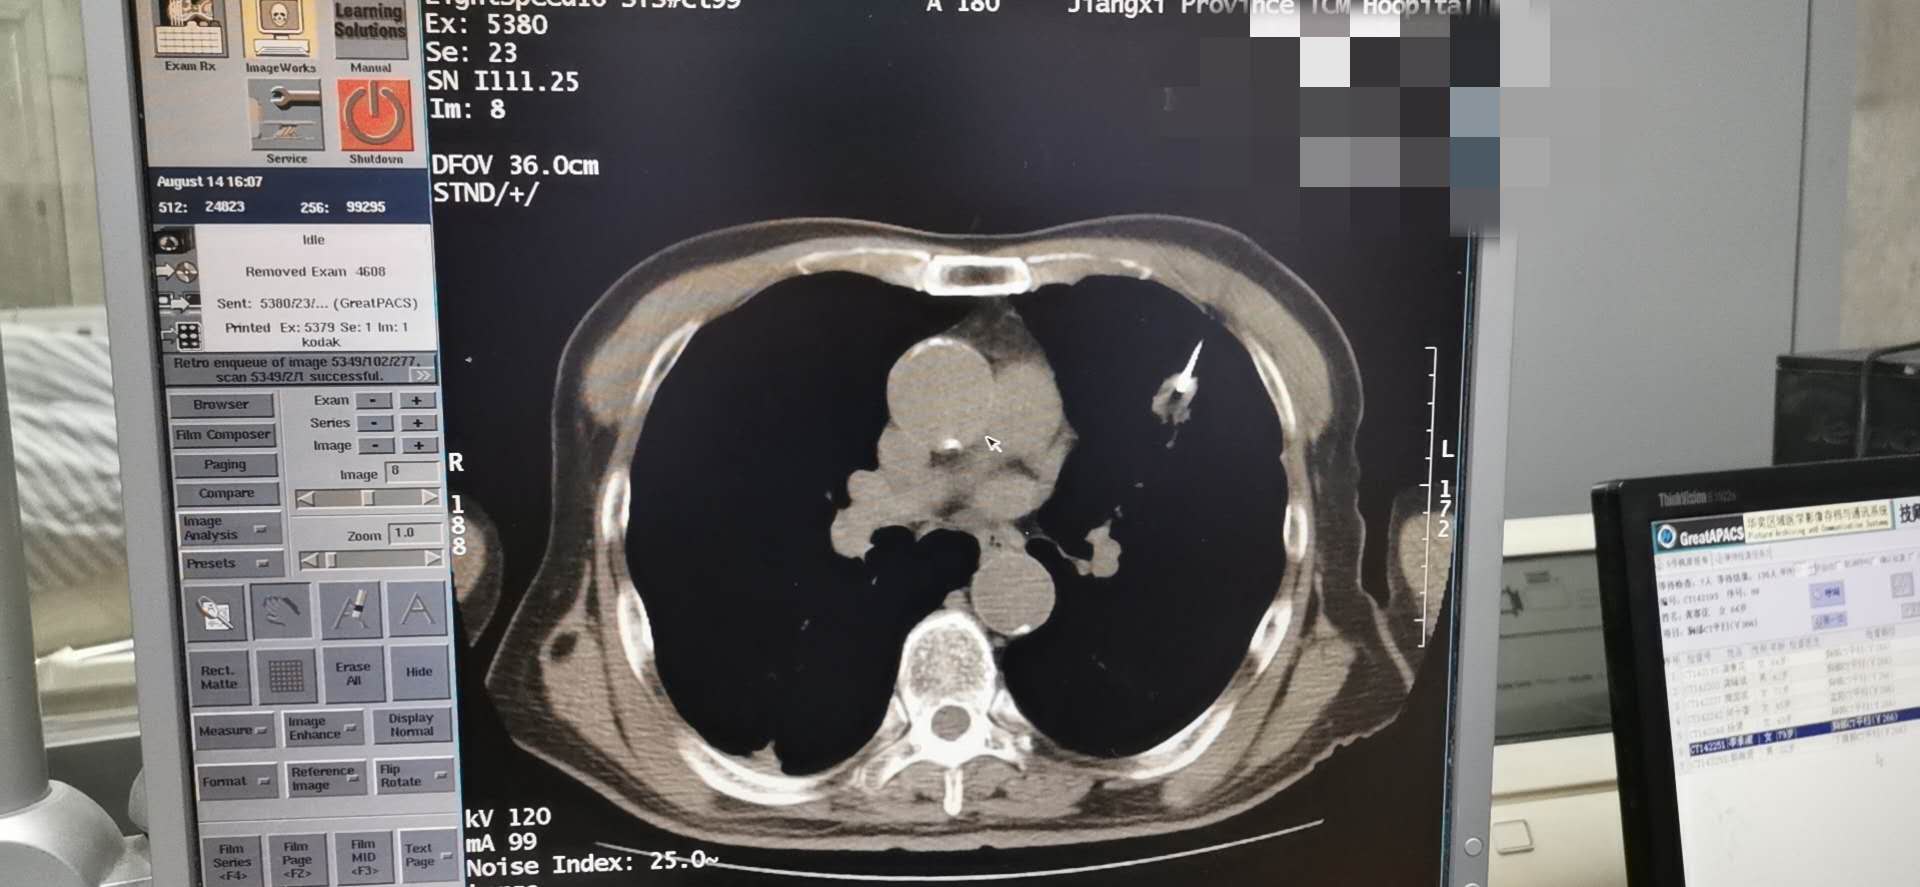

肺癌的发病率及死亡率高居恶性肿瘤之首,早诊断及早治疗尤为关键。 CT引导经皮穿刺肺活检诊断肺部疾患CT引导下穿刺适用范围广,临床应用最多。CT横断层扫描有良好的空间分辨率和密度分辨率,可准确显示病灶的大小、位置及内部情况,以及与血管等周围结构的解剖关系,尤其适用于定位难度大、病灶在肺门及纵隔附近者。当肿块与肺不张、阻塞性肺炎混合后,有时需行增强扫描才能确定肿块的实际大小。方法是指先作CT扫描确定病灶最佳的穿刺点,进针深度和角度,而后进行穿刺活检。常规CT下不能直接观察进针状况,必须在确定进针点后估算进针深度及进针方向,进针后再次扫描确认后方可行穿刺活检。CT引导下穿刺精确度高,对于0.5~1cm的病灶也可在CT导引下成功活检。因此对常规方法未能确诊的肺部结节病变、空洞病变、双肺弥漫性病变及纵隔肺门占位病变,应用CT引导下肺穿刺抽吸和切割针活检能取得较满意结果。尤其直径≤2cm肺部结节活检的准确性较高而并发症较低,可作为肺内孤立性小结节灶定性诊断的首选方法,其操作简单、安全、可靠。

为明确诊断及指导下一步治疗方案。我科洪禹霖副主任医师、张峰浩医师、吁佳副主任护师精诚配合下于8.14日成功完成一例肺小结节穿刺术,术后无明显气胸及出血并发症、患者安返病房。